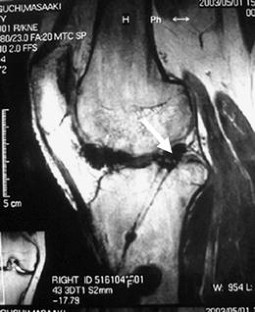

Fig. 1